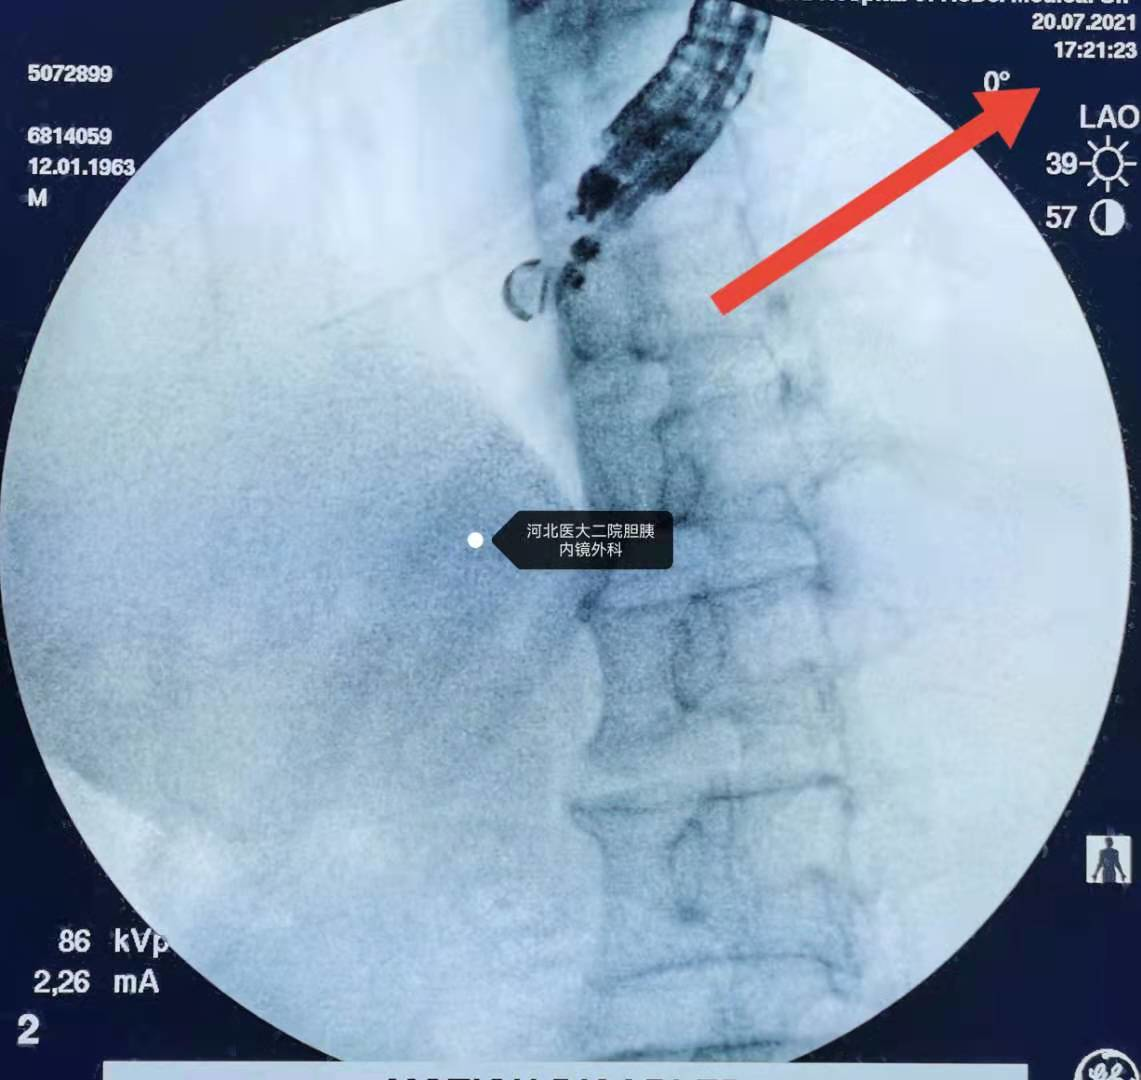

造影。

继续造影。